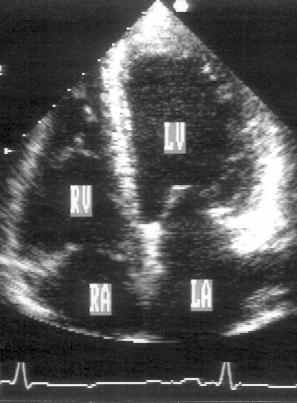

Апикальная четырехкамерная позиция (рис. 2.11)

Апикальная четырехкамерная позиция сердца — одна из важнейших в двумерной эхокардиографии, так как она позволяет одновременно увидеть предсердия, желудочки, оба атриовентрикулярных клапана, межжелудочковую и межпредсердную перегородки.

Рисунок 2.11. Апикальная четырехкамерная позиция. LV — левый желудочек, LA — левое предсердие, RV — правый желудочек, RA — правое предсердие.

Чтобы правильно получить апикальную четырехкамерную позицию, нужно точно установить датчик над областью верхушки сердца, и плоскость сечения должна проходить через митральный и трехстворчатый клапаны так, чтобы регистрировалось полное их открытие: в этом случае сечение проходит через длинные оси обоих желудочков. Чтобы лучше рассмотреть отдельные структуры (легочные вены, межпредсердную перегородку в верхней ее части) или, например, направить ультразвуковой луч для допплеровского исследования точно по потоку, нужно слегка изменять положение датчика.

На изображении ближе всего к датчику расположена верхушка левого желудочка, ниже — левый желудочек (справа) и правый (слева). Межжелудочковая перегородка проходит посередине изображения. Атриовентрикулярные клапаны располагаются горизонтально в систолу и открываются в диастолу в сторону верхушки сердца. Передняя створка митрального клапана находится медиально, задняя латерально. Септальная створка трехстворчатого клапана прикрепляется к межжелудочковой перегородке (медиально), передняя створка трехстворчатого клапана (самая большая из трех створок) — к латеральной части кольца трехстворчатого клапана. Задняя створка трехстворчатого клапана в этой позиции не видна. Передняя створка митрального клапана прикрепляется на уровне верхнего участка мембранозной части межжелудочковой перегородки. Септальная створка трехстворчатого клапана прикрепляется ближе к верхушке (на изображении — выше) — на уровне среднего участка мембранозной части межжелудочковой перегородки. Поэтому на изображении трехстворчатый клапан оказывается на 5—10 мм выше митрального. Это может существенно помочь в идентификации желудочков при транспозициях магистральных сосудов (митральный клапан всегда соответствует левому желудочку, трехстворчатый — правому).

Апикальная четырехкамерная позиция — одна из основных при исследовании глобальной и локальной сократимости левого желудочка. К сожалению, эндокард в области верхушки левого желудочка в этой позиции, как и во всех других, часто виден не вполне отчетливо. На изображении левое предсердие ограничено в этой позиции митральным клапаном, межпредсердной перегородкой, верхней и боковой стенками. Легочные вены впадают в левое предсердие в области его верхне-боковой и верхне-медиальной стенки. Правый желудочек виден от верхушки до трехстворчатого клапана и от межжелудочковой перегородки до свободной боковой стенки. Слева в нижней части изображения находится правое предсердие.